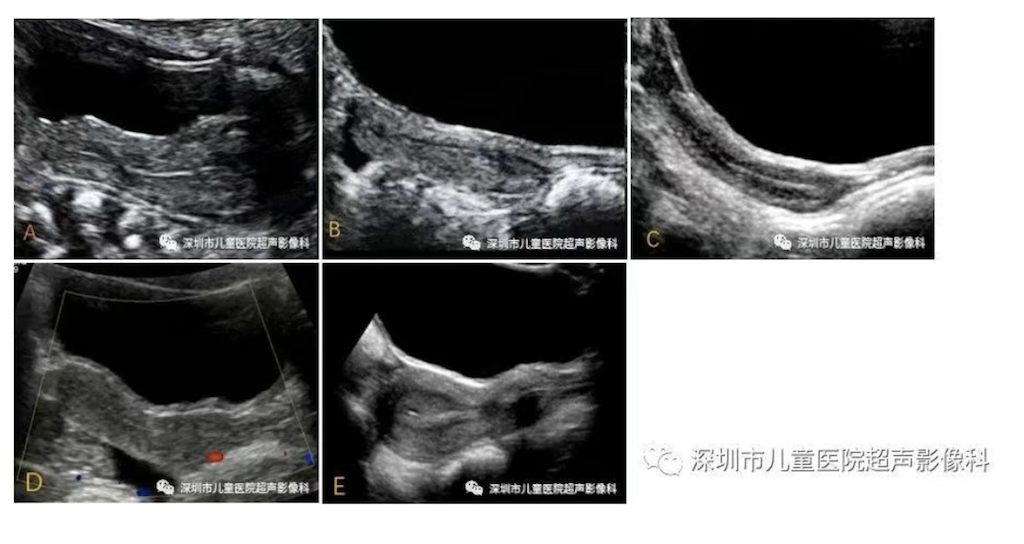

性早熟指性器官及第二性征提前发育。女性性早熟指的是女童7.5岁前出现乳房发育、体毛生长或10岁前出现月经初潮,可导致患儿生长潜能受损及心理健康受影响。本科普读物包含性早熟超声诊断标准,以及不同时期儿童的卵巢、子宫和乳腺发育的超声表现及结果判读。

关键词性早熟  超声  女童